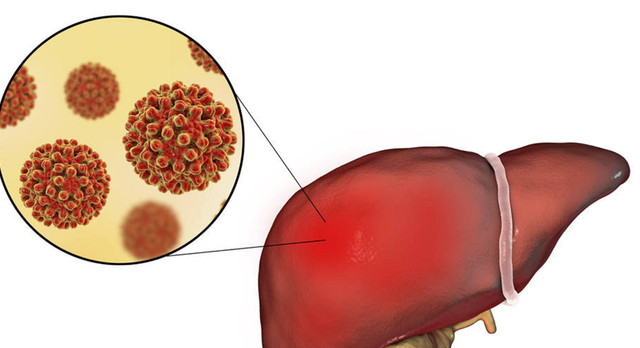

从病毒到肿瘤,“隐形杀手”的演变过程

从病毒到肿瘤,“隐形杀手”的演变过程中国是乙肝大国,也正因如此,我们拥有全球最多的肝癌患者。据《中国肿瘤登记年报》显示,肝癌在我国癌症死亡率中长期位列前三。乙肝病毒,是肝癌发生的“幕后黑手”之一。

但不是所有乙肝患者都会得肝癌。这个过程像是一场“长跑”——从病毒感染、到肝脏炎症、再到肝硬化,最后才可能演变成肝癌。而这中间,往往是十年、二十年的时间。

有研究指出,在未接受规范治疗的乙肝病毒携带者中,20年内发展为肝癌的风险可达15%-25%。特别是那些病毒复制活跃、ALT长期升高的人群,风险更高。

真正可怕的是,很多人根本不知道自己是乙肝病毒携带者。没有症状、不去查、不重视,就这样一步步走到了癌症的边缘。